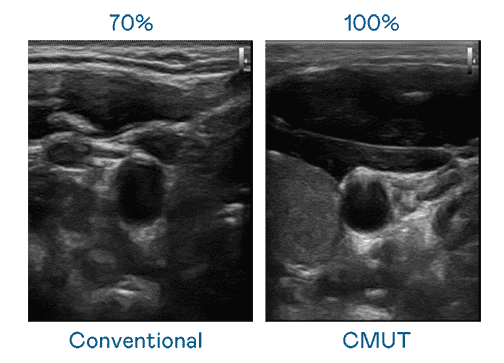

CMUT 技术是一种用电容式微机电元件来产生超音波讯号的技术。。。与传统 PZT 压电式技术相比,,,CMUT 频宽增加 30%,,,,更宽频的超音波讯号让影像解析度大幅提升,,,是实现高影像品质医疗超音波扫描、、促进精准医疗发展的关键技术。。。

大频宽带来超清晰影像

超音波影像的解析度高低,,,,首先取决于探头能发出的讯号频宽。。杏悦2 CMUT 可提供高清晰的超音波讯号,,提供高频宽、、高灵敏度、、、影像纹理细节更高的超音波影像,,协助医护人员缩短影像判读时间及利用精准的医疗影像进行诊断。。。